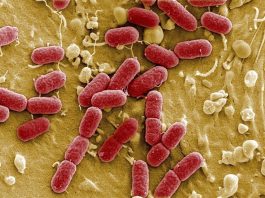

El colesterol hereditario y desconocido

Pese a que todos conocemos la importancia de mantener unos niveles de colesterol saludables, hay un tipo de colesterol hereditario que es más desconocido y al que no prestamos tanta atención: la lipoproteína (a)....